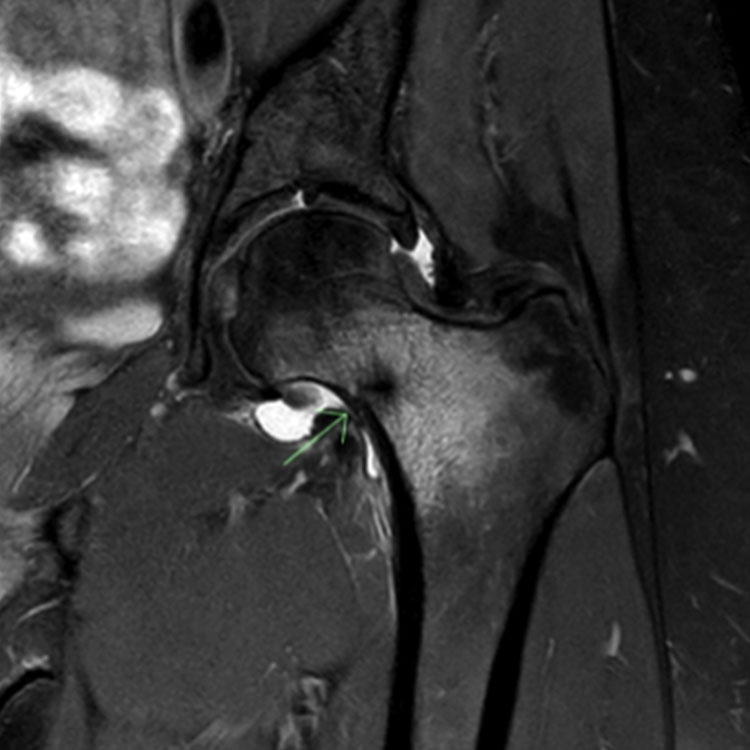

내측 복사뼈 (Medial malleolus): 본질적으로 불안정하고 비유합되기 쉬우므로 고위험 피로골절로 간주됩니다. X-ray나 CT에서 골절선이 보이지 않는 경우 4~6주 동안 적극적인 고정(엄격한 비체중 부하)이 필요합니다. 골절선이 명확한 경우 **개방 정복 및 내고정술(ORIF)**이 선택 치료입니다.